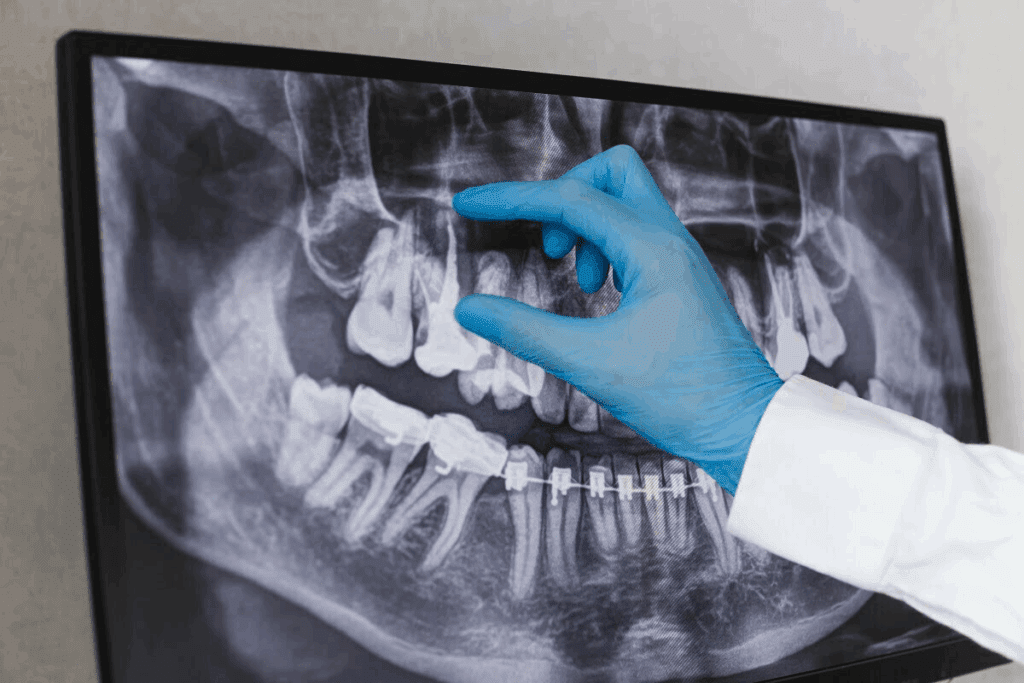

Dental technology keeps getting better, and the panoramic dental x-ray is a big step forward. It shows the whole mouth in one picture. This helps dentists see everything they need to know panoramic film dental.

This dental imaging technique shows all teeth, jaws, sinuses, TMJ, and bones. It gives dentists a wide view. This is key for finding problems and planning treatments.

It’s important to know about panoramic dental X-rays to see their value in dentistry. These X-rays show the whole mouth in one picture. They are key for diagnosing problems.

A panoramic dental X-ray shows the whole mouth in one picture. It includes teeth, jaws, and more. A special X-ray machine takes pictures as it moves around the head.

It’s important to know how panoramic dental X-ray machines work. They capture a wide view of the teeth, jawbone, and facial bones. This helps in diagnosing dental issues.

The machine rotates around the patient’s head during a panoramic dental X-ray. This rotational scanning process creates a detailed, two-dimensional image of the dental structure.

The machine’s arm moves in an arc around the patient’s head. The X-ray generator and detector work together to capture the images. This process takes a few seconds to a minute, depending on the machine and settings.